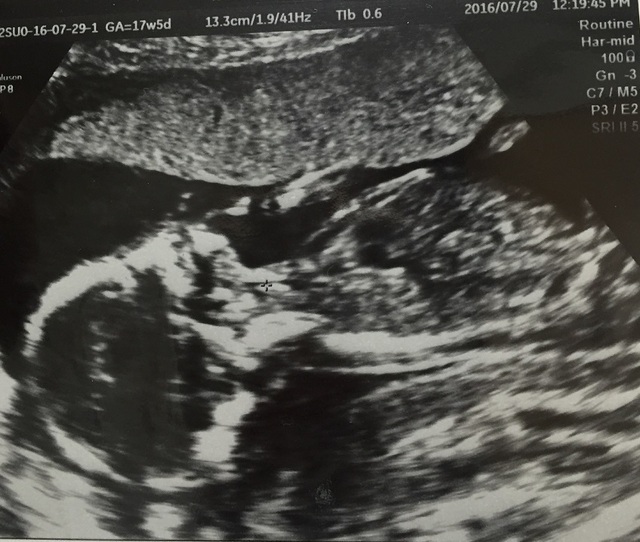

17週3日(17w3d・性別不明)|りんころ_ さん(22歳)

エコー写真撮影時のエピソード:

待ちに待った4週間ぶりの健診で、この日から初めての腹部エコーでした。 どんな風に写るんだろうとワクワク。

なんと、足を組んでいるではないか!(笑)私よりも看護師さんが「この子足組んでるわぁー!ほら見て!もぉ~!」と興奮されていました。